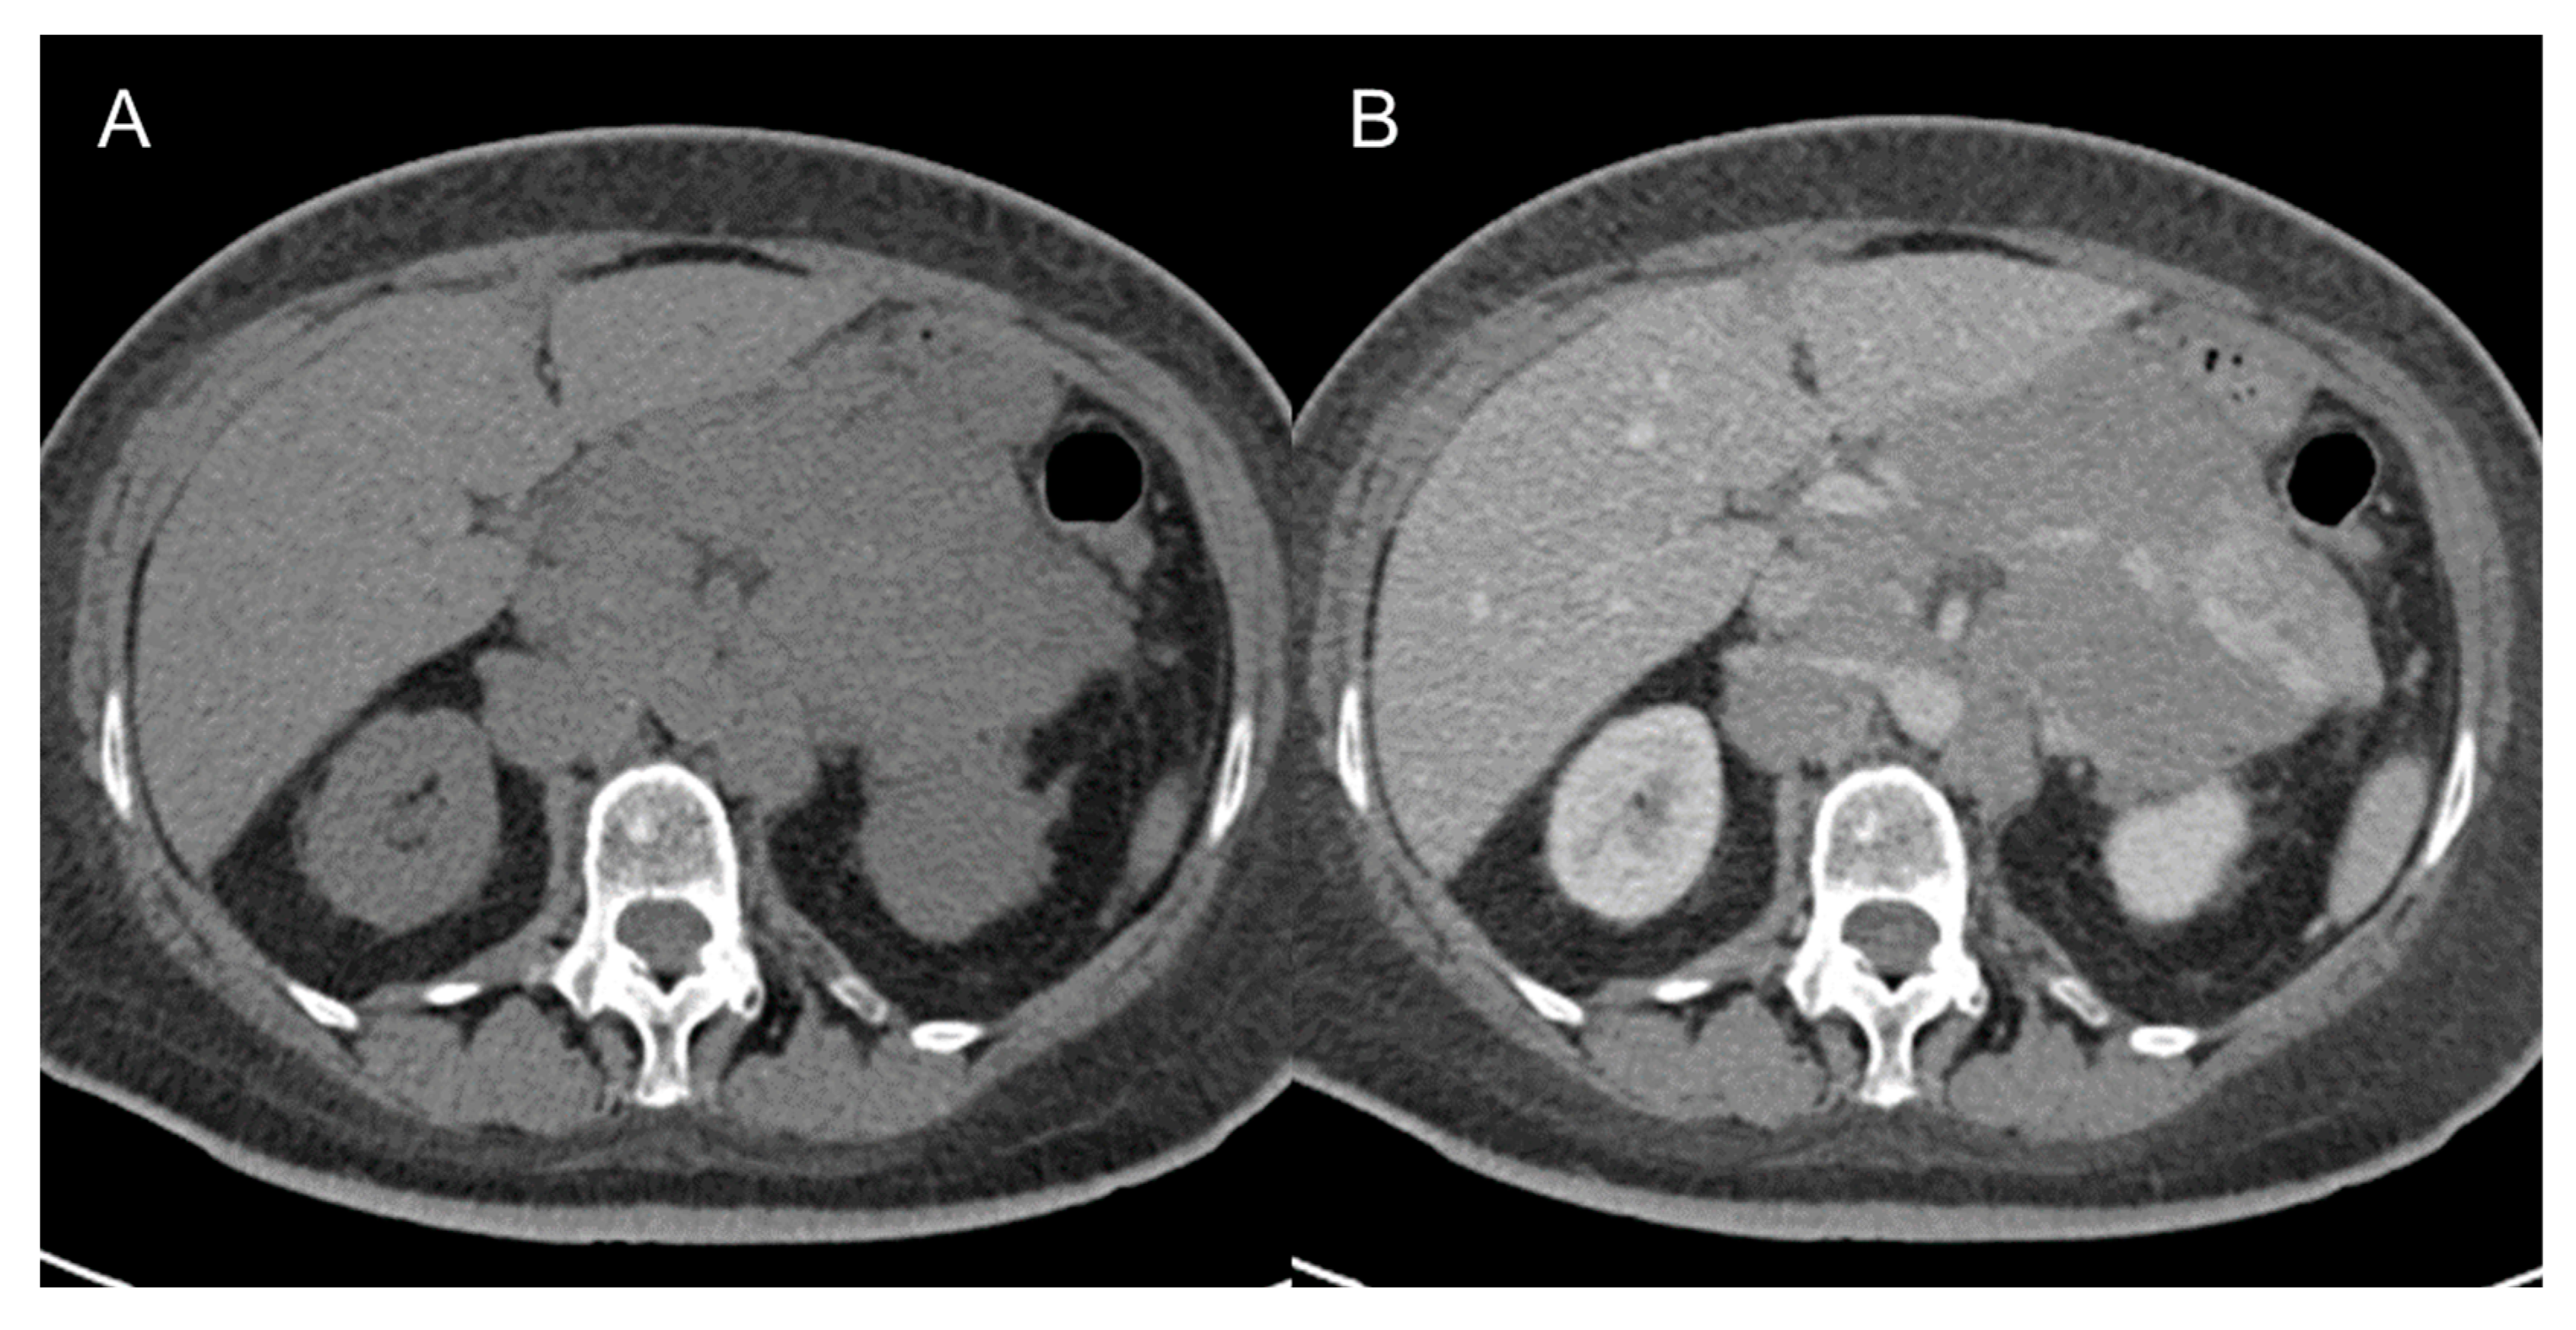

5. Complications

Complications are usually related to tumor invasion of adjacent structures or to mass effect caused by the tumor and include hydronephrosis, pulmonary embolisms secondary to compression of inferior cava vein, nerve compression, bowel obstruction (Figure 11) [49], and even intestinal perforation [50]. Postoperative complications are divided into early and late complications and include pulmonary embolism, ileus, fluid collections, hemorrhage [49], splenic injuries, sepsis, multisystem organ failure. For these reasons, guidelines recommend that immediate postsurgical care should be held in subspecialized facilities [2,19,51,52,53].

Figure 11.

Bowel obstruction in 38-year-old woman with metastatic leiomyosarcoma. Axial (A,B) and coronal (C) CT images on the venous phase show dilatation of small bowel loops with air–fluid levels secondary to the presence of metastatic masses (arrow) in the pelvis.